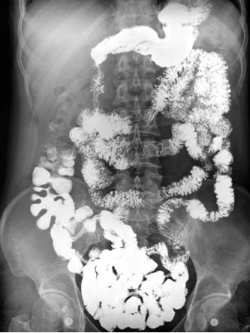

•下消化道造影:30至45分钟

下消化道造影(钡剂灌肠):测试可能会令人感到不舒服,有些患者会突发腹部痉挛,并且许多患者发现该检查消耗大量体力。钡剂造影会使您的粪便在试验后几天变成浅色,并有可能导致便秘。极少数情况下,钡剂会导致肠道阻塞。